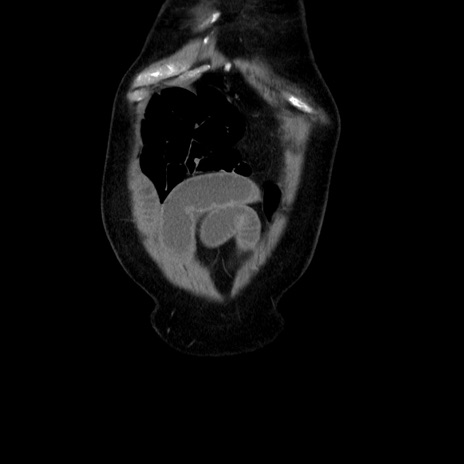

症例30(冠状断像)

【症例】80歳代男性

【主訴】臍周囲痛

【現病歴】約6時間前から臍下部痛が出現。次第に腹部膨隆・背部痛も生じてきたため来院。背部痛の場所は変化しない。

【身体所見】意識清明、BT 36.3℃、BP  131/87mmHg、P 87bpm、SpO2 100%(RA)、臍周囲自発痛・圧痛あり、反跳痛なし、自発痛部位に一致して板状硬あり、腹部膨隆、腸雑音減弱、CVA tenderness両側陰性。